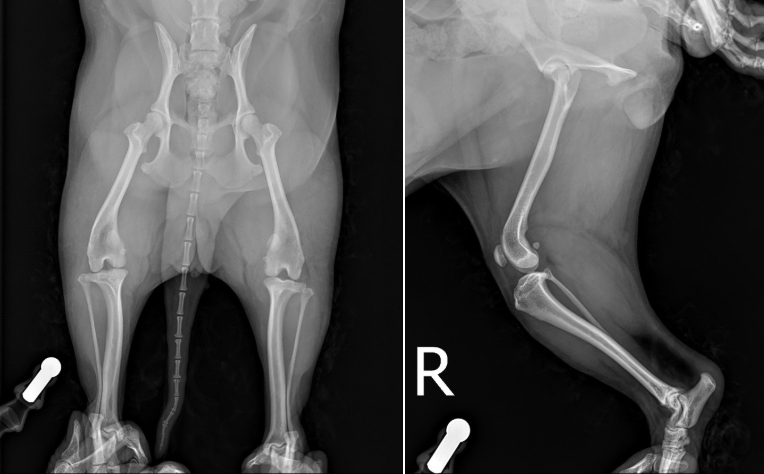

엑스레이 상 십자인대가 끊어지면서 무릎이 앞으로 밀리는 소견이 확인되었습니다.

또한 십자인대가 끊어지게 되면 급성 관절염 및 부종 소견이 동반될 수 있는데 그 또한 확인되어 종합적으로 봤을 때, 환자는 우측 십자인대 완전 단열로 인해 이미 관절염도 진행되고 있고 통증이 있는 것으로 고려되었습니다.

TPLO 수술을 계획하기 위해서는 엑스레이 촬영 했을 때 좌측에 보이는 calibration ball 을 같이 포함하여 촬영을 해야합니다. ▼

* 관절내 부종이 확인됩니다.

* 무릎을 굽힌 상태로 엑스레이 촬영 시 십자인대 단열로 인해 무릎이 앞으로 전방변위되는 것이 확인됩니다.